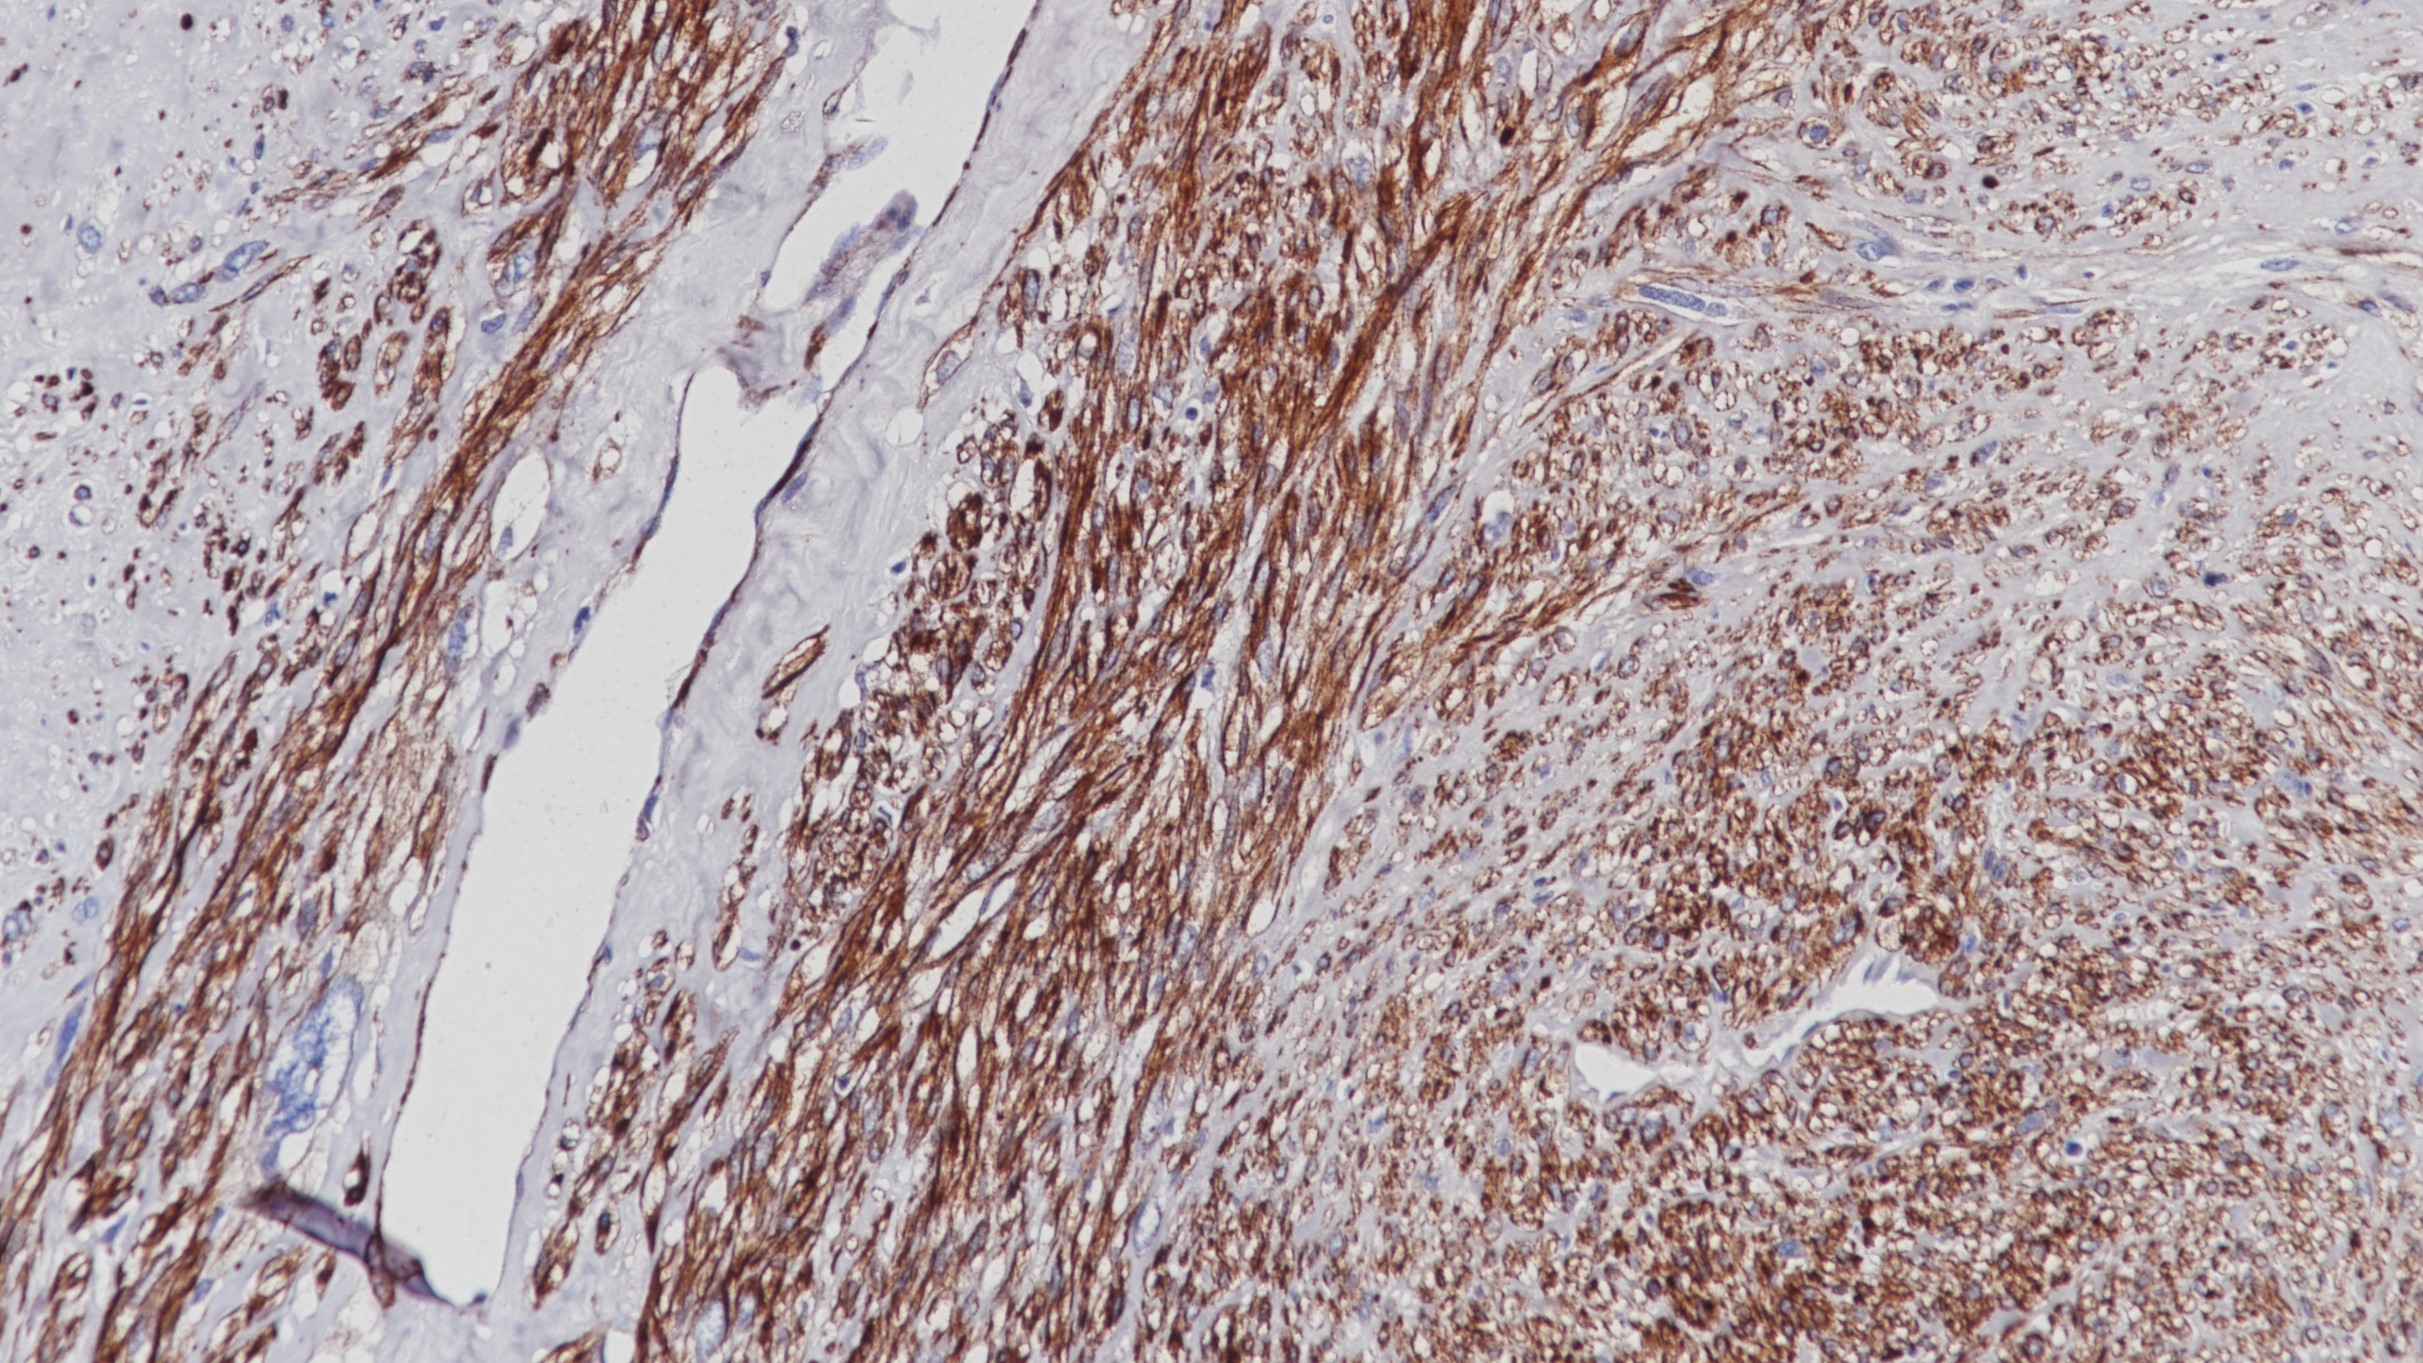

1. Mohamed A, et al. SOX10 Expression in malignant melanoma, carcinoma, and normal tissues. Appl Immunohistochem Mol Morphol. 2013 Dec; 21(6):506-10.

2. Mollaaghababa R, Pavan WJ. The importance of having your SOX on: role of SOX10 in the development of neural crest-derived melanocytes and glia. Oncogene. 2003 May 19; 22(20):3024-34.